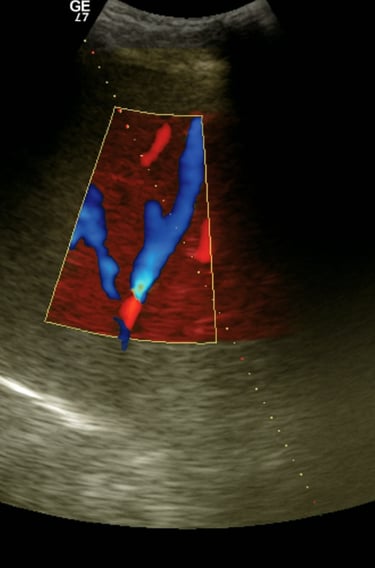

Ultrasonografía del cuadrante superior derecho para identificar vena hepática media o derecha permeable

Ecografía de la vena hepática media